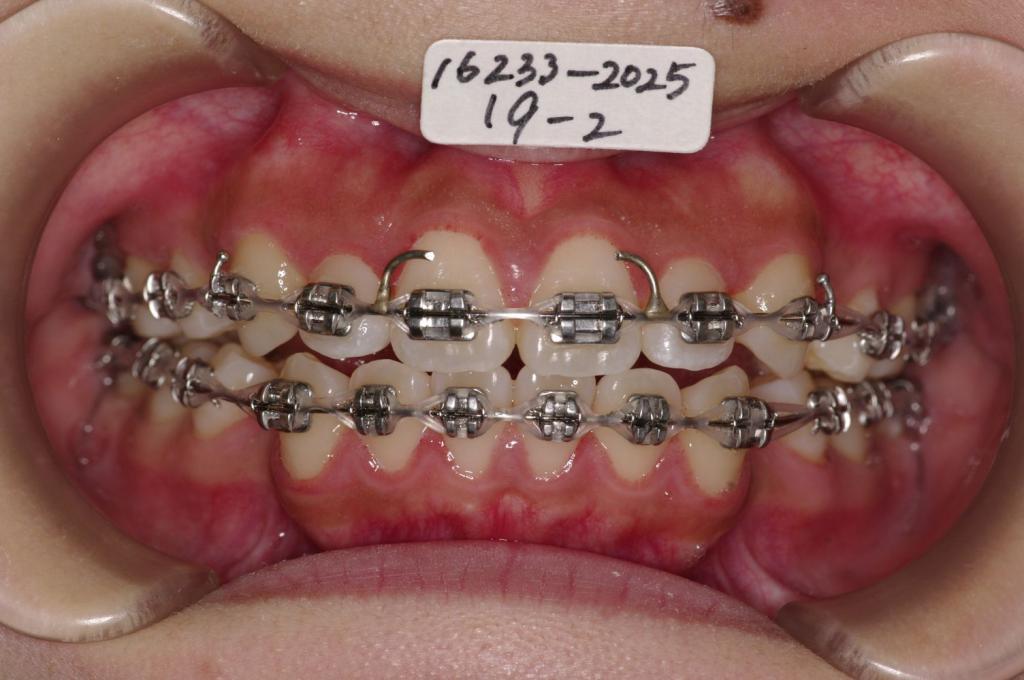

- 前歯、出っ歯・開咬の矯正治療

- 前歯が出ている